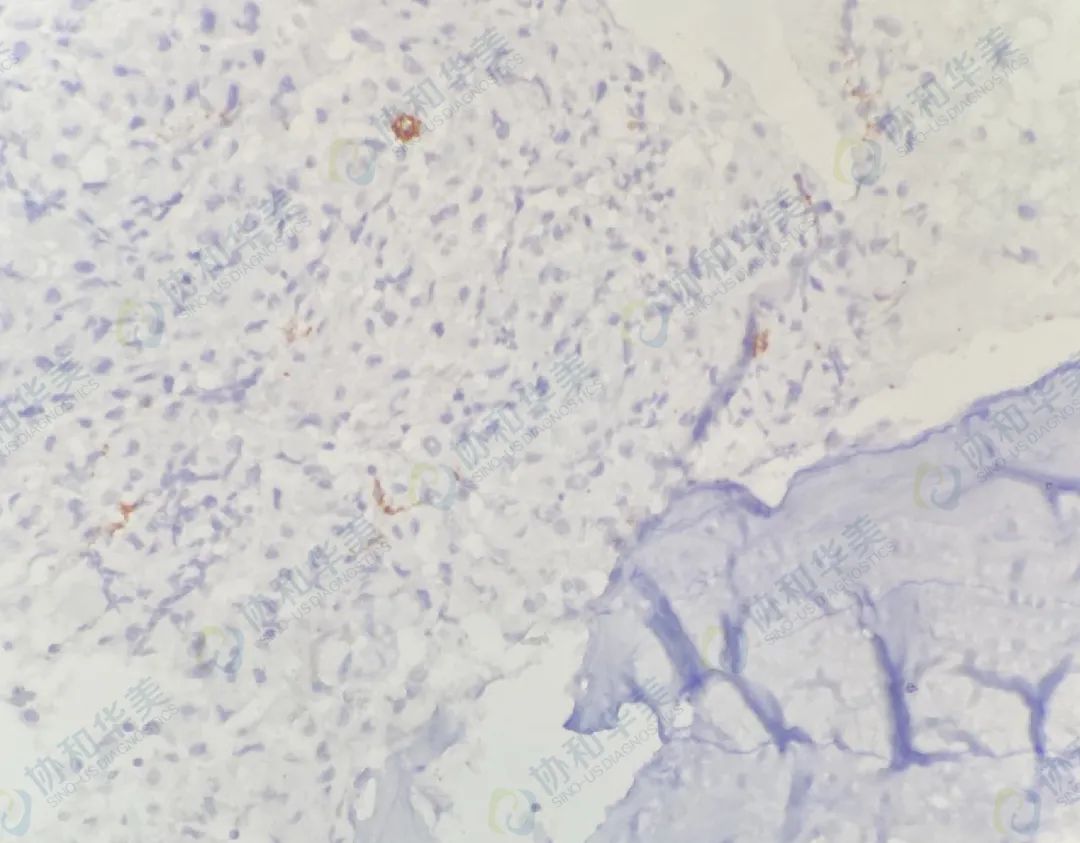

病理切片

CD117                                             Tryptase